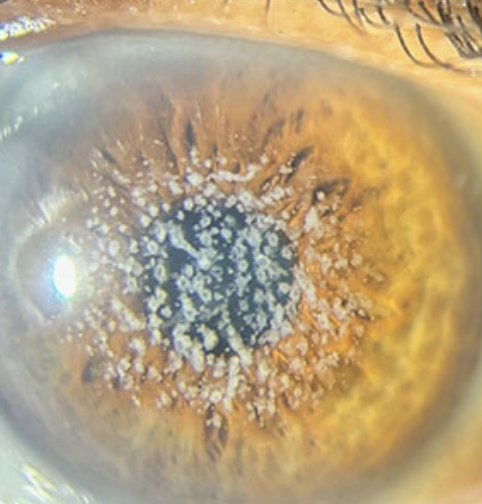

Corneal Dystrophies

One of the 6 Corneal Abnormalities

Group of inherited disorders that cause abnormal deposits or growths in the corneal tissue

Examples include Fuchs’ dystrophy and lattice dystrophy

Nuclear Cataract

One of the 4 Lens Abnormalities

Appear gray when seen with a flashlight

Appear as a black spot against the red reflex when seen through an opthalmoscope